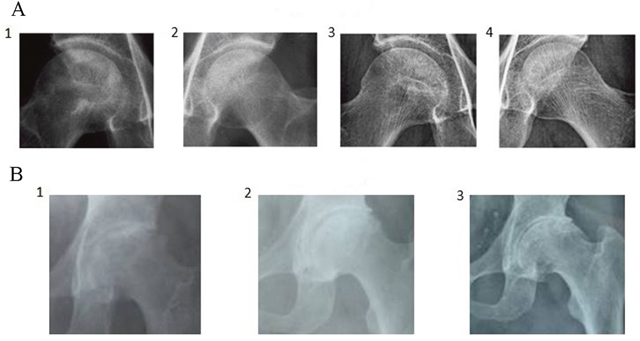

We evaluated the efficacy of BSP in patients with avascular necrosis of the femoral head using a double-blind, randomized controlled trial. A total of 300 ONFH patients were included in this study (Table 2A). Of these, 100 were salvia tablets were used as the control pills. The effective rate of BSP was 82%, which was significantly higher than that of the control pills (Table 2B). The rate of improvement in pain relief, hip joint function, and claudication was significantly better in the BSP group than in the control group (Table 2C–2F). Sex, age, or etiological subtypes had no effect on the response to BSP (Table 2G–2I). Representative cases are shown in Figure 3A and 3B. Moreover, BSP could significantly ameliorate ONFH as evaluated by X-ray analysis (Table 2J). The results from routine blood, urine, heart, liver, and kidney tests showed that BSP was safe, and BSP significantly ameliorated ONFH as evaluated by MRI analysis (Table 2K, Figure 4A and 4B).

Figure 3: Representative case of osteonecrosis of the femoral head (ONFH) by X-ray analysis. (A) 52-year-old male patient, alcoholic. 1 and 2: The density of the femoral head was not uniform and bone trabeculae disappeared, especially on the right side. 3 and 4: After treatment with the bone-strengthening pill (BSP), the pathological radiographic findings disappeared and the patient resumed work. (B) 58-year-old male patient, no clear etiology was determined. 1: The outline of the femoral head was disrupted with the disappearance of the joint space and loss of bone trabeculae. 2: After treatment with BSP, the surfaces of the femoral head became smooth with joint space restored and clear margins of bone trabeculae. The patient started light work after treatment. 3: A 16-year follow-up showed a smooth surface of femoral head, clear joint space, and bone trabeculae.